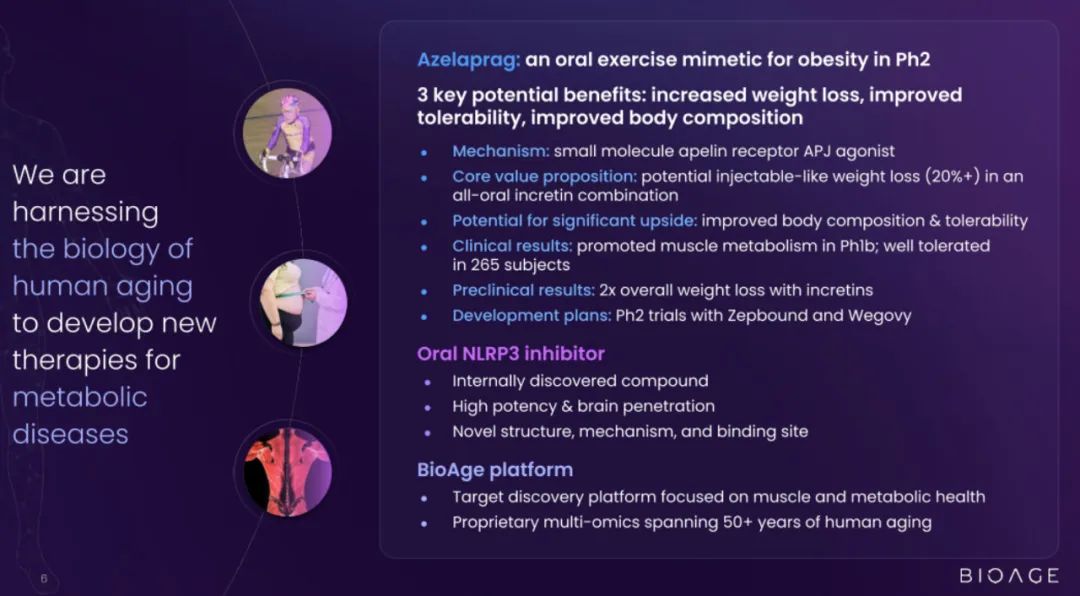

BioAge Labs是一家临床阶段的生物制药公司,致力于针对人类衰老生物学,开发肥胖等代谢疾病的治疗产品候选物。

BioAge Labs的主要关注点是代谢疾病,这是全球最大的医疗保健挑战之一。BioAge Labs的主要候选产品 Azelaprag是一种口服小分子,在8个 1 期临床试验中,265 名受试者的耐受性良好。在临床前肥胖模型中,azelaprag 显示出能够使胰高血糖素样肽-1 受体 (GLP-1R) 激动剂诱导的体重减轻增加一倍以上,同时恢复健康的身体成分并改善肌肉功能。

这些临床前结果得到BioAge Labs在卧床老年人中进行的 1b 期临床试验的支持,在该试验中,BioAge Labs观察到在 10 天内接受 azelaprag 治疗的受试者的肌肉萎缩减少、肌肉质量保持良好并且新陈代谢得到改善。

BioAge Labs正在进行的 STRIDES 临床试验将评估阿泽拉普拉格与礼来公司 (Lilly) 以 Zepbound® 为商品名销售的替泽帕肽联合使用的效果,预计在 2025 年第三季度公布顶线结果。第二项 2 期临床试验将评估阿泽拉普拉格与诺和诺德以 Wegovy® 为商品名销售的索马鲁肽联合使用的效果,预计在 2025 年上半年启动。

BioAge Labs还计划在 2025 年上半年启动一项针对阿泽拉普拉格单药治疗的胰岛素敏感性概念验证试验,以支持潜在的适应症扩展。我们还在开发口服小分子脑渗透性 NLRP3 抑制剂,用于治疗由神经炎症引起的疾病。

BioAge Labs预计将在 2025 年下半年提交 NLRP3 抑制剂的新药临床试验申请 (IND),如果获得批准,将于2026年上半年启动1期临床试验。